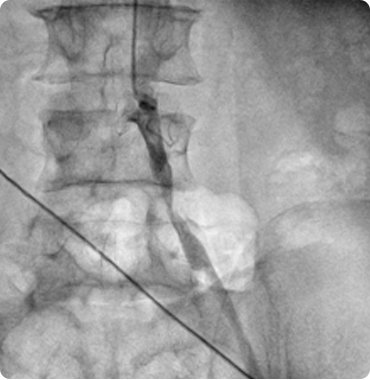

Together with a team of trained staff, his goal is to provide top care so that patients can achieve and maintain a healthy heart. He has done hundreds of angiographies and angioplasties...